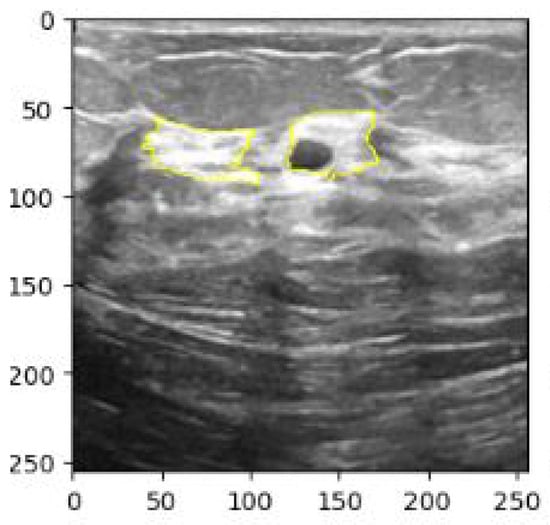

- Furthermore, we present an automated boundary extraction using Local Interpretable Model-agnostic Explanations (LIME) which highlights the boundary extraction of breast lesions from BUS images and provides the interpretable explanations on the predictions of the proposed multi-stage transfer learning model.

3.3. LIME for an Improved Interpretability from BUS Images